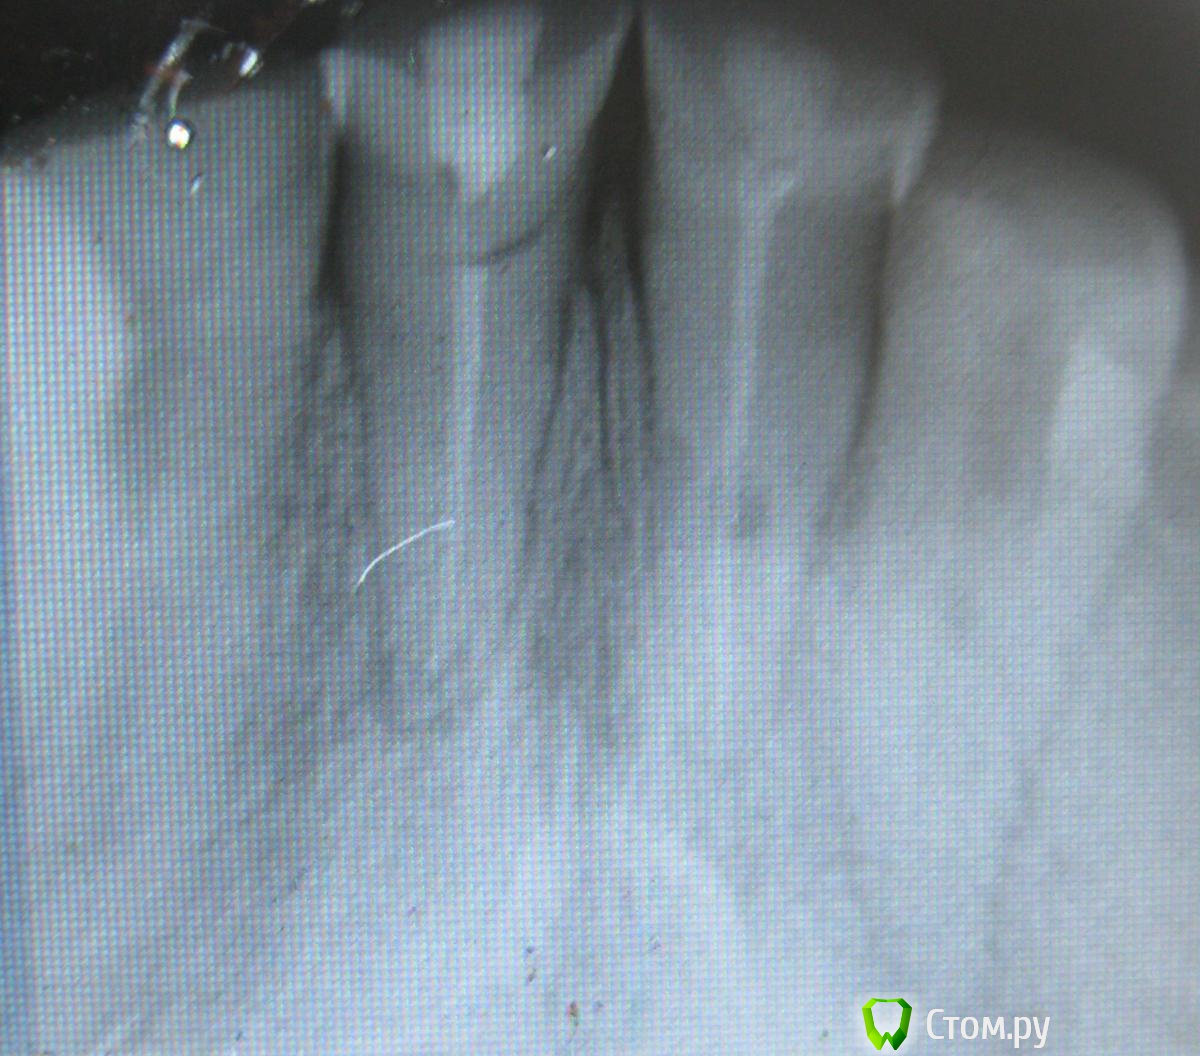

Пациент 49 лет, пришел в клинику с жалобами на боли 21 зуба при накусывании, также хочет протезироваться, зуб 21 поставлен диагноз травматический периодонтит. По словам пациента фронтальные зубы стерлись в течении 3х лет, жевал только фронтом. Коллеги что посоветуете с протезированием? Извиняюсь за качество снимков, Спасибо.

первое - панорамный снимок.

После этого что-то можно решать с протезированием.

Скорее всего придется снимать штампованный мост, под которым, опять же, скорее всего будут гнилые зубы.